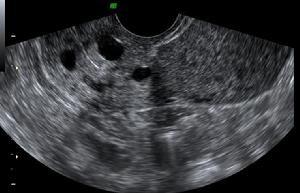

11月5日,在丈夫的陪伴下,她来到了医院做彩超,想看一看小家伙们的状态都怎么样了。

医生称侯女士的子宫里面有8个孕囊,初步断定她怀的是八胞胎,侯女士还没能从这个巨大的冲击中缓过来。

浑浑噩噩的就回到了家中,6天后,她担心医生是看走眼误诊了,便再次前往医院做了孕检。

事实证明,医生确实“看走眼了”,她怀上的实际是9胞胎,这次不仅能够看到子宫内9个紧紧依偎的孕囊,还能看到胚胎的心管一下一下的搏动。